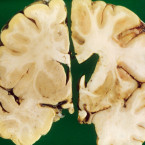

Naděje pro nevyléčitelné Huntingtonovou chorobou. Spouští se klinická studie léčby

Nová genová terapie nevyléčitelné Huntingtonovy choroby, na jejímž vývoji se podíleli i čeští vědci, vstupuje ve Spojených...